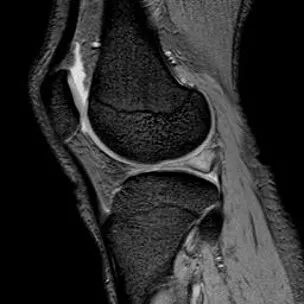

1、纵行撕裂2、撕裂方向和半月板长轴方向平行3、垂直或斜行的III级高信号

(半月板纵行撕裂)